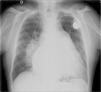

The electrocardiogram showed atrial fibrillation with ventricular response of 55 bpm, right bundle branch block and left posterior hemiblock. The chest X-ray after pacemaker implantation (Figure 3) showed a cardiothoracic ratio of >50%, dilatation of the right atrium and of both pulmonary arteries, and pulmonary vasculature enhancement. The transthoracic echocardiogram showed a dilated left atrium; interventricular septal hypertrophy, with preserved left ventricular function, and dilated right chambers with annular dilation of the tricuspid valve, causing moderate tricuspid valve regurgitation, with pulmonary artery systolic pressure calculated at 50 mmHg (moderate pulmonary hypertension); and a dilated pulmonary artery and mild pulmonary regurgitation. No morphological defect of the atrial septum was found, or flow across the atrial septum; the ventricular septum also showed no morphological defect.

Chest X-ray may show enlarged pulmonary arteries due to pulmonary hypertension or cardiomegaly and evidence of congestive heart failure may be present.